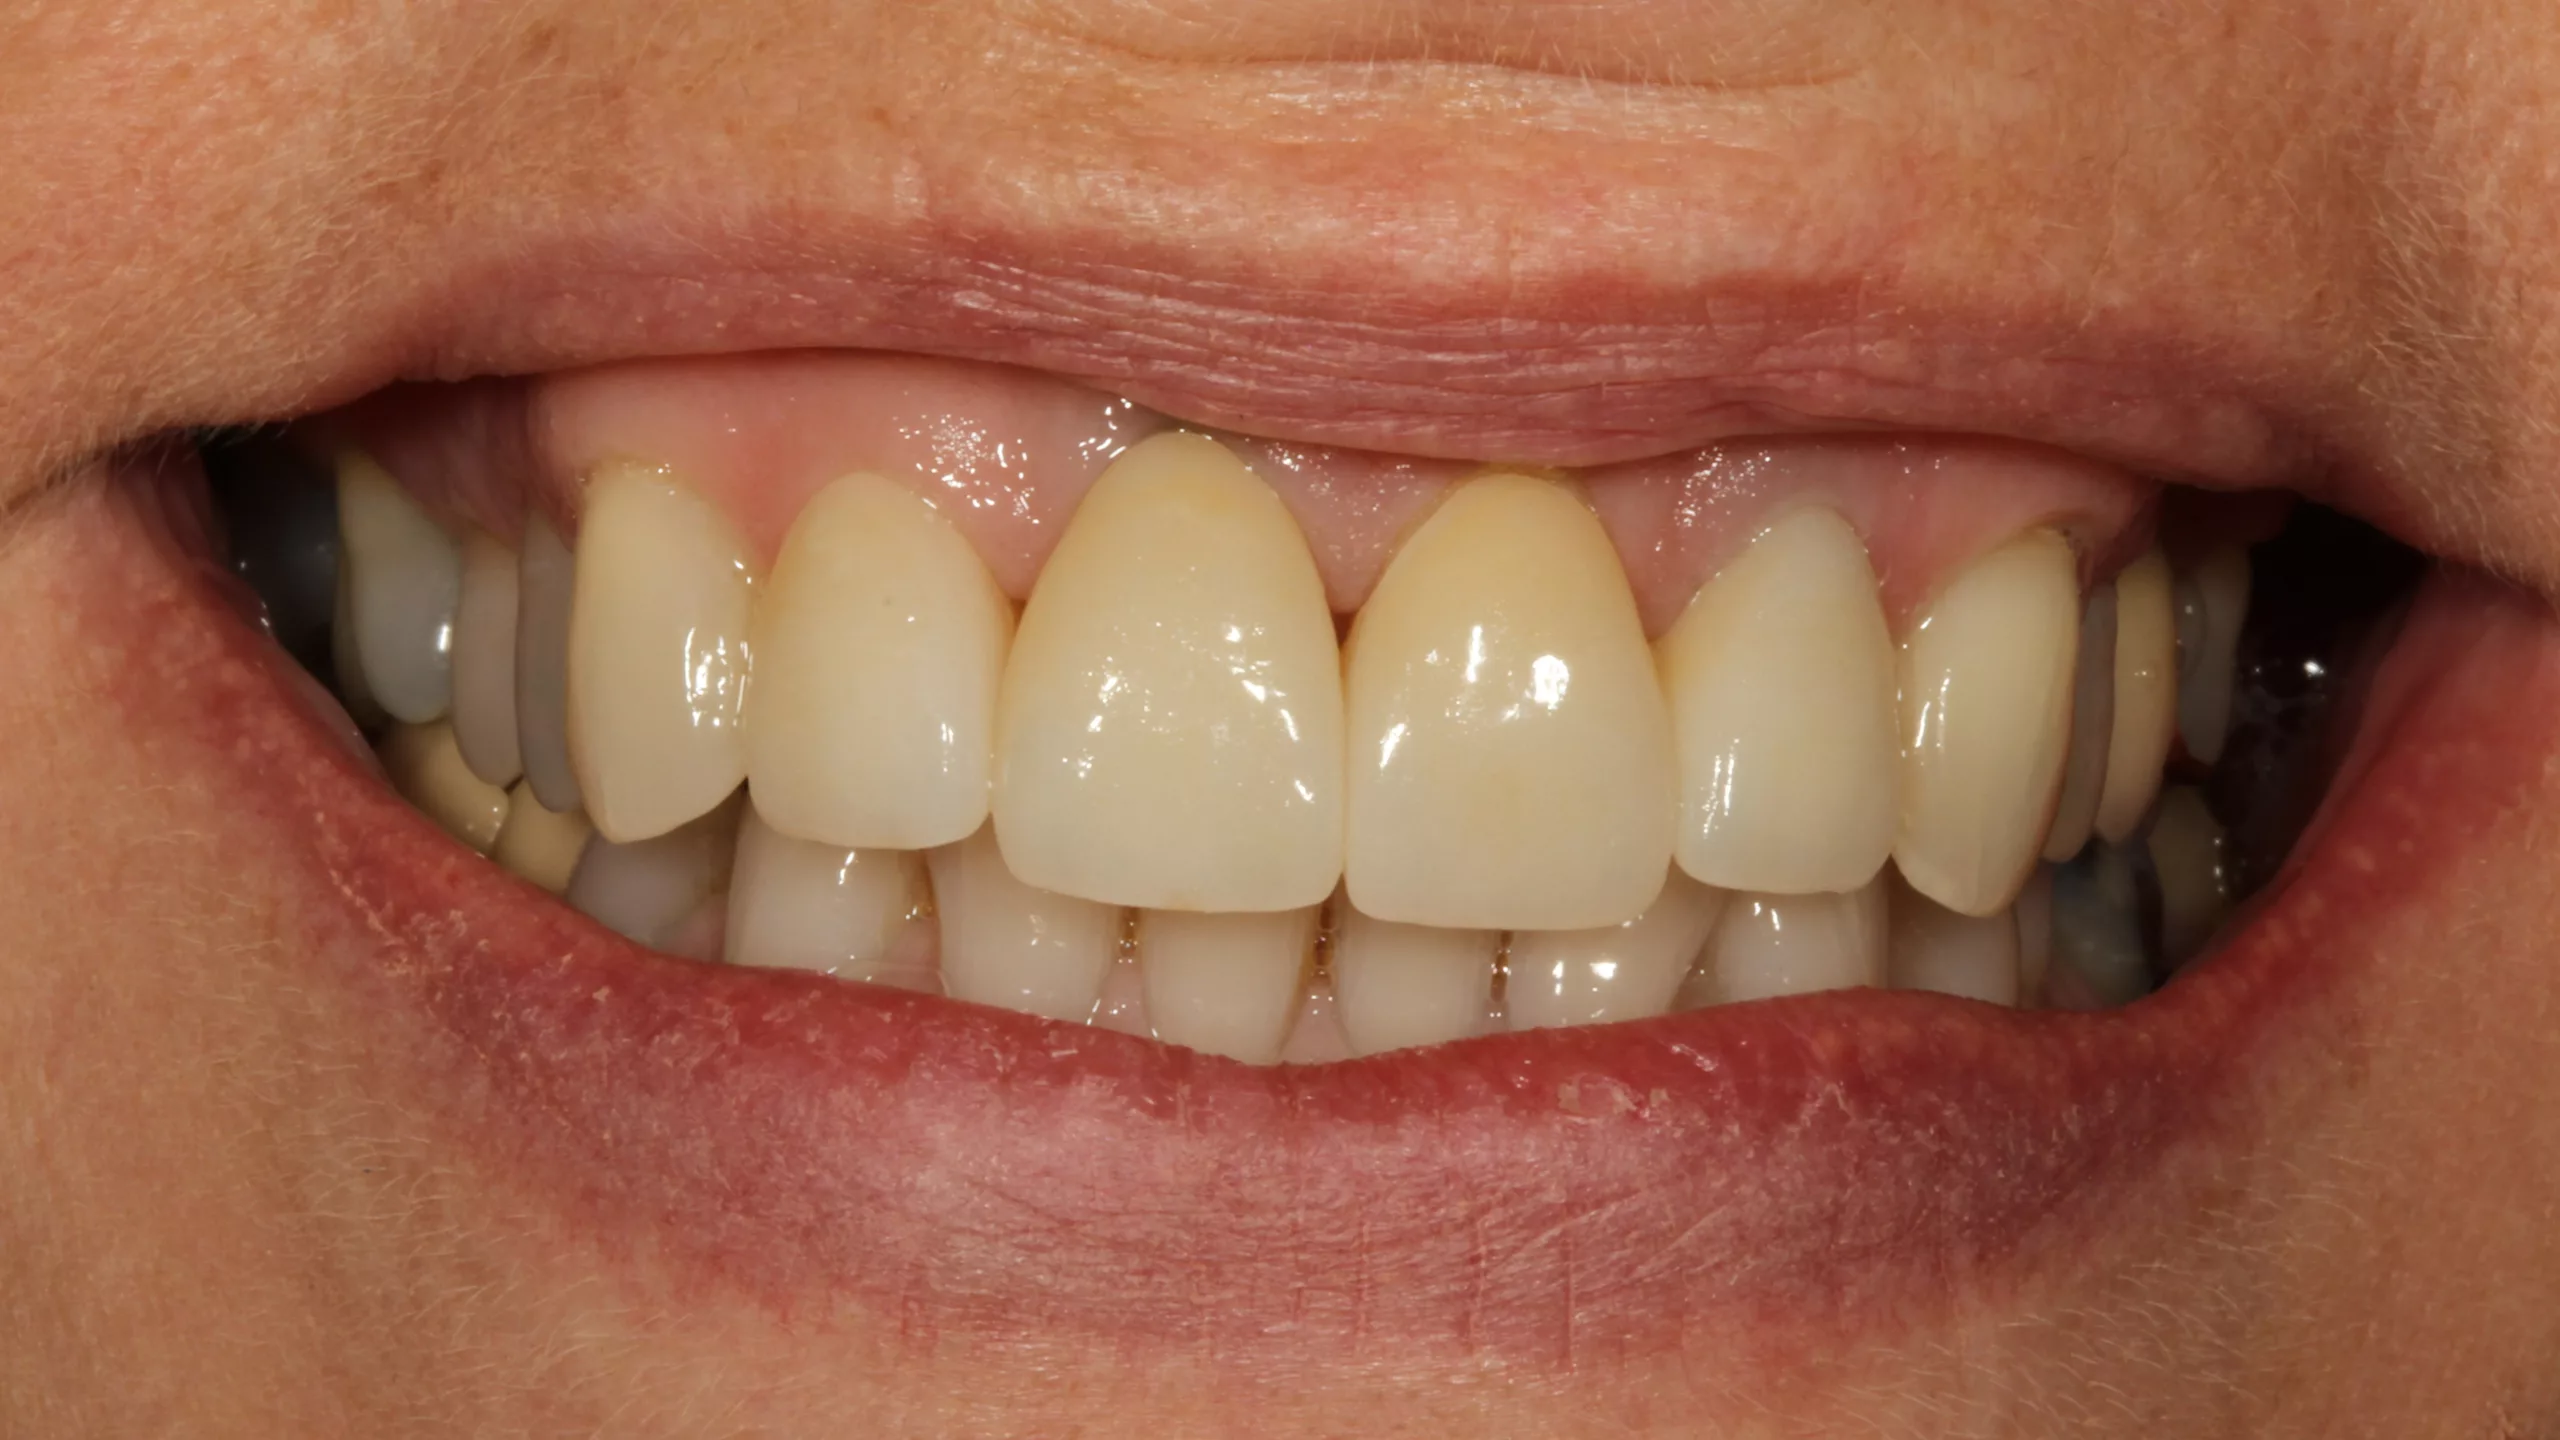

Bei der 55-jährigen Patientin bestand der Wunsch nach einer ästhetischen Neuversorgung ihrer Frontzahnsituation (Abb. 29 und 30). Die Zähne 11 und 22 waren wurzelkanalbehandelt, alle Schneidezähne wiesen ältere, große, farblich nicht mehr passende Kompositversorgungen auf. Die Neuversorgung wurde aufgrund der Stabilität und der besseren Abdeckung verfärbter Zahnbereiche aus einem monolithischen Zirkonmaterial gefertigt, die labial additiv verblendet wurden (Abb. 31 und 32).

Die Abbildungen 35 und 36 zeigen die eingesetzte Arbeit und das zufriedene neue Lächeln der Patientin. Leider konnte im vorliegenden Fall die äußerst dunkle Farbe des Zahnstumpfes von Zahn 22 nicht komplett kaschiert werden. Die Verwendung einer bei Visalys Cem-Core ebenfalls zu Verfügung stehenden, sehr opaken Variante des Materials wurde kurzzeitig erwogen, dann allerdings wiederum verworfen, weil die doch sehr hohe Opazität die Gesamtästhetik vielleicht eher negativ beeinträchtigen könnte. Ein Beispiel zur Verwendung dieses opaken Befestigungs- und Aufbaumaterials zeigt später der letzte Fall dieses Beitrags.